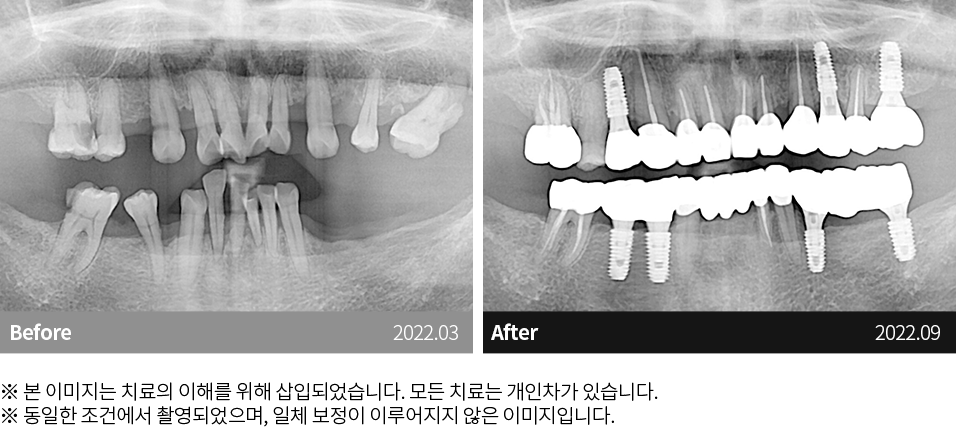

자연치아 보존원칙

고난이도케이스 치료

임플란트